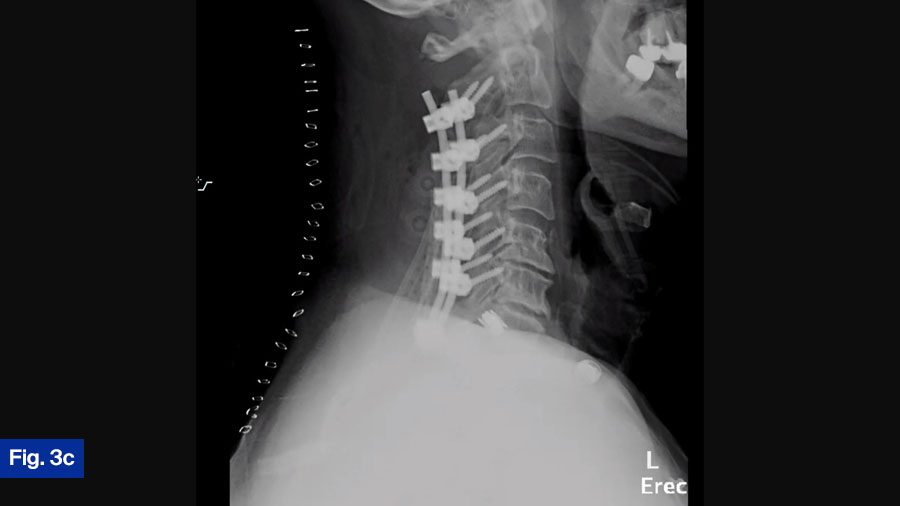

Actual treatment

The patient was taken urgently for C2-T1 laminectomy, and C2-T1 posterior cervical fusion (Figure 3c). The patient was covered postoperatively with IV Nafcillin for 2 months, and then transitioned to oral antibiotics. The patient was doing well at final follow-up and was able to ambulate slowly, but without difficulty. Neurologic deficits resolved.